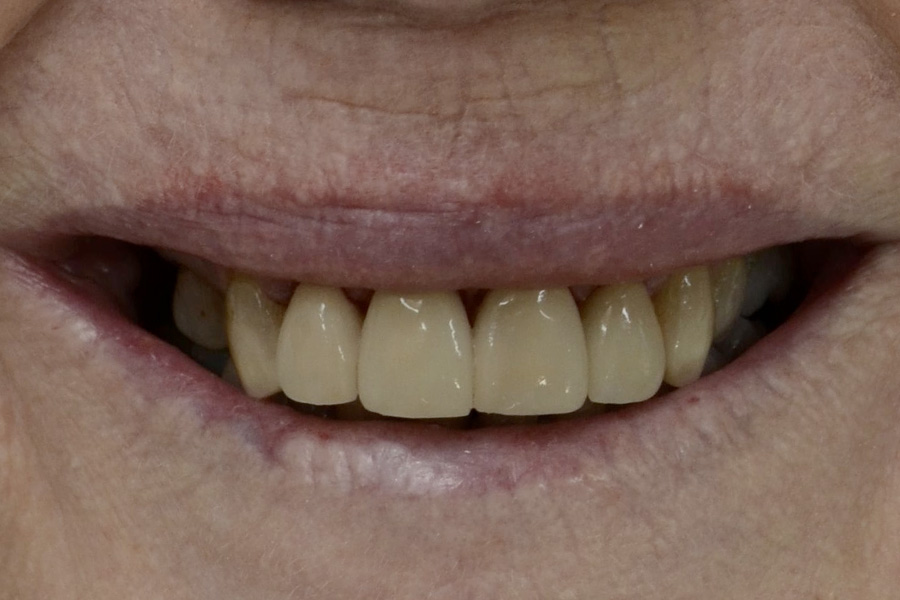

The following cases had stained and failing white fillings. Interestingly one person even had very old gold inlays in their front teeth.

They were replaced with esthetic ceramic veneers. As seen in these images changes to shape and size within limits can also be achieved along with the color.

Sue